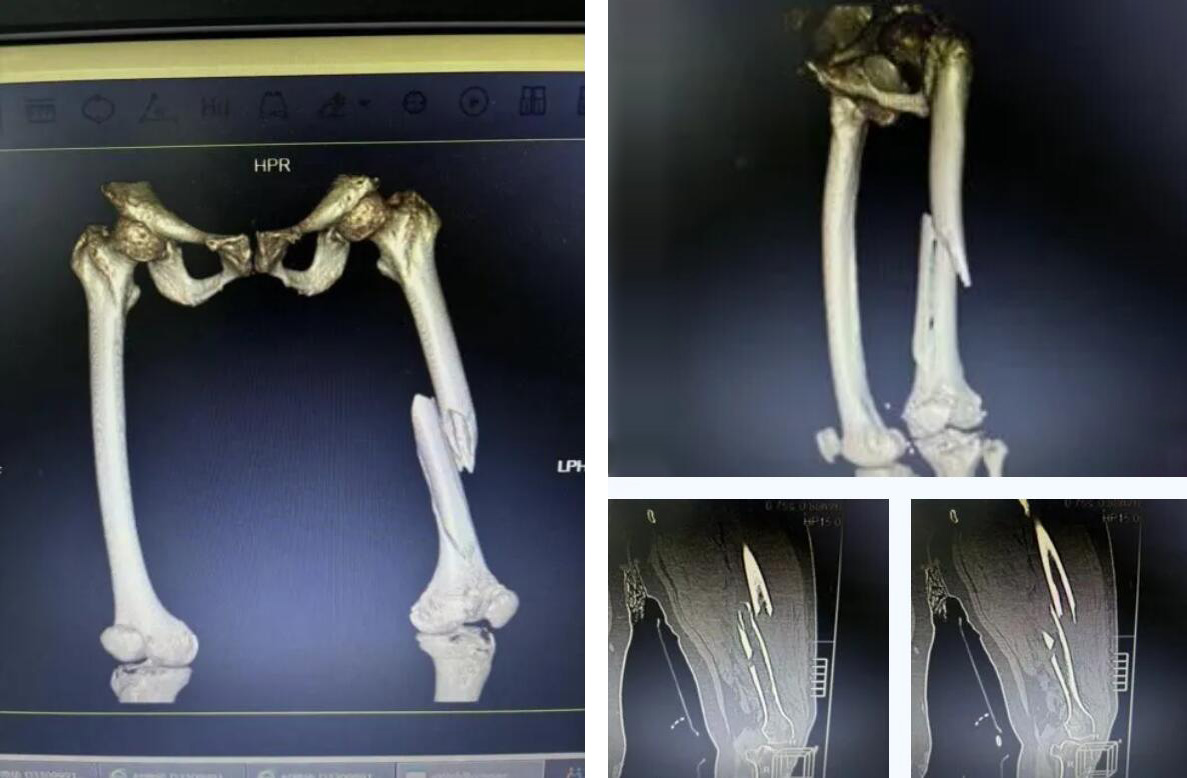

術(shù)前患者骨折CT影像

股骨,即人體的大腿骨,是全身最長的骨骼,對于高齡老人,尤其是超過90歲的超高齡老人而言,髖部骨折常被稱為“人生最后一次骨折”,死亡率極高。

而俞奶奶的股骨中段的多段骨折,手術(shù)難度和風險更是呈幾何級數(shù)增加,傳統(tǒng)的開放手術(shù)創(chuàng)傷大、出血多,老人脆弱的心肺功能難以承受。